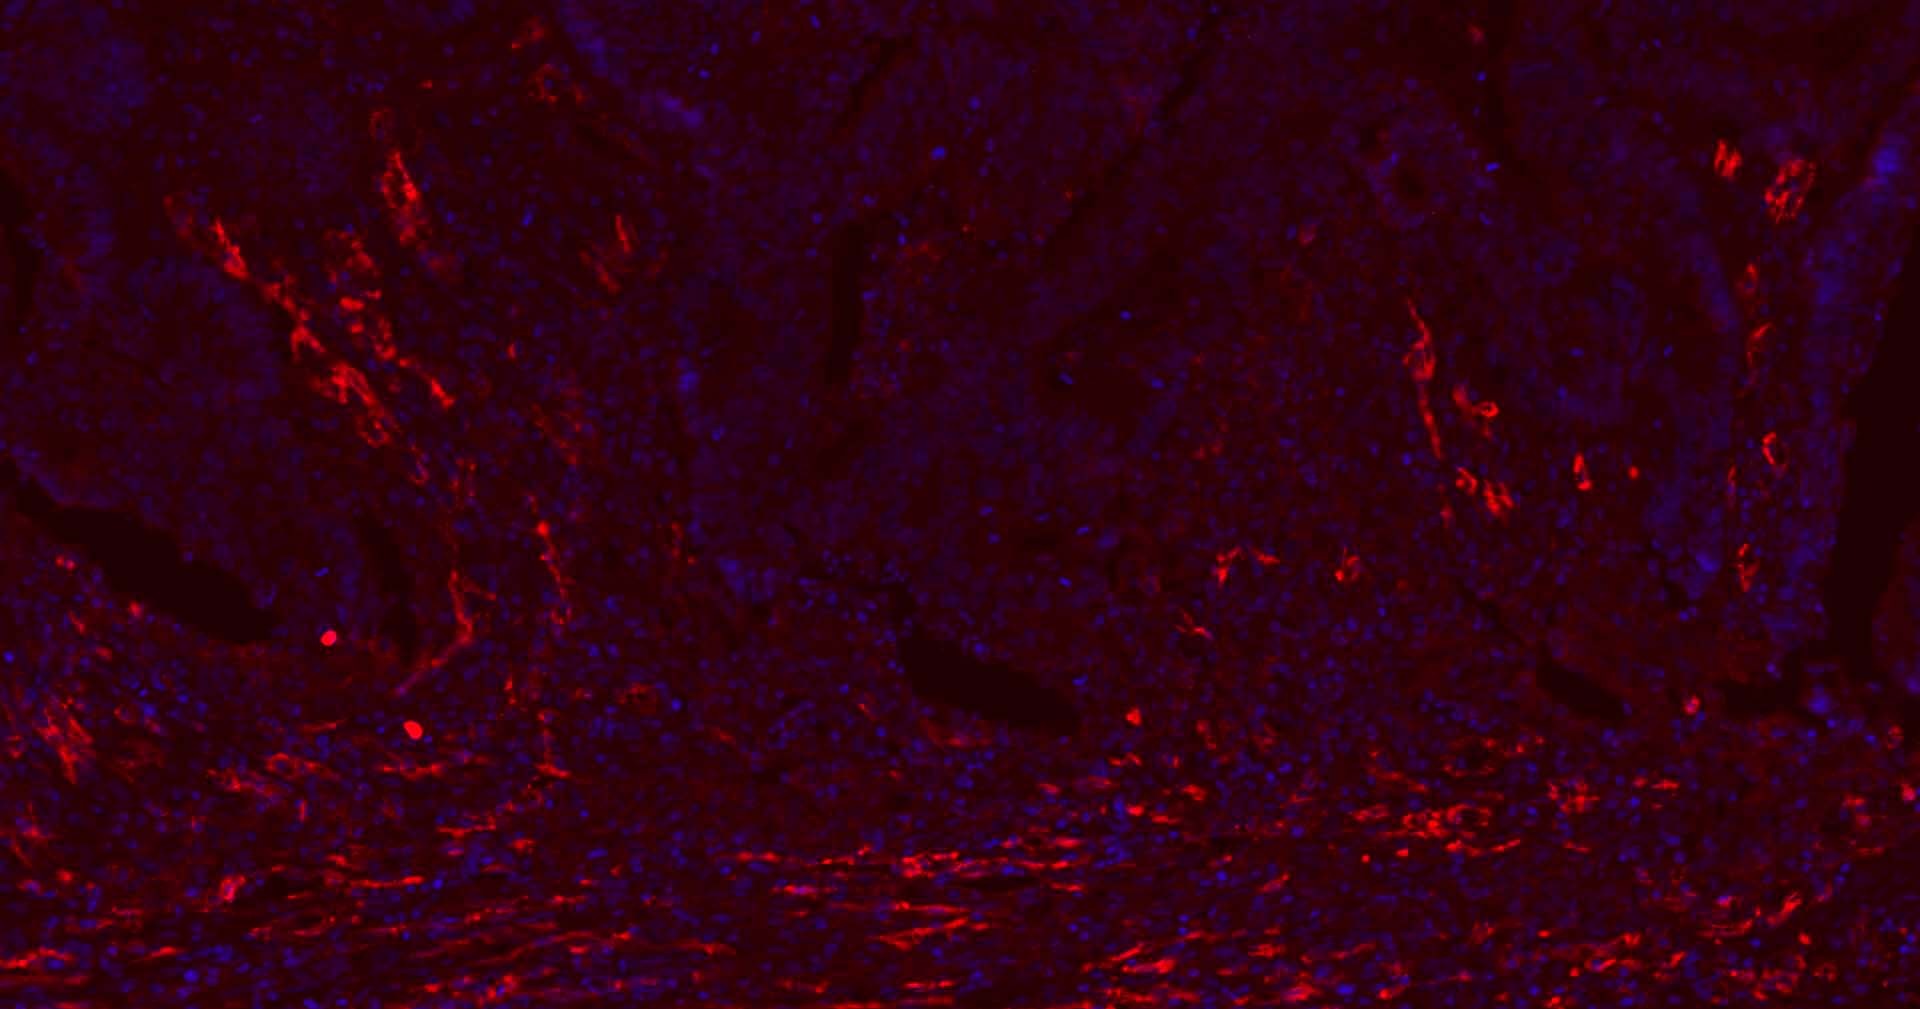

7. Paraformaldehyde-fixed, paraffin embedded Human Colon Cancer; Antigen retrieval by boiling in sodium citrate buffer (pH6.0) for 15 min; Antibody incubation with CD31 Monoclonal Antibody, Unconjugated (TMAB-00354) at 1:200 overnight at 4°C. Followed by conjugated Goat Anti-Rabbit IgG antibody (Red), DAPI (blue) was used to stain the cell nucleus.

8. Paraformaldehyde-fixed, paraffin embedded Human Liver; Antigen retrieval by boiling in sodium citrate buffer (pH6.0) for 15 min; Antibody incubation with CD31 Monoclonal Antibody, Unconjugated (TMAB-00354) at 1:200 overnight at 4°C. Followed by conjugated Goat Anti-Rabbit IgG antibody (Red), DAPI (blue) was used to stain the cell nucleus.